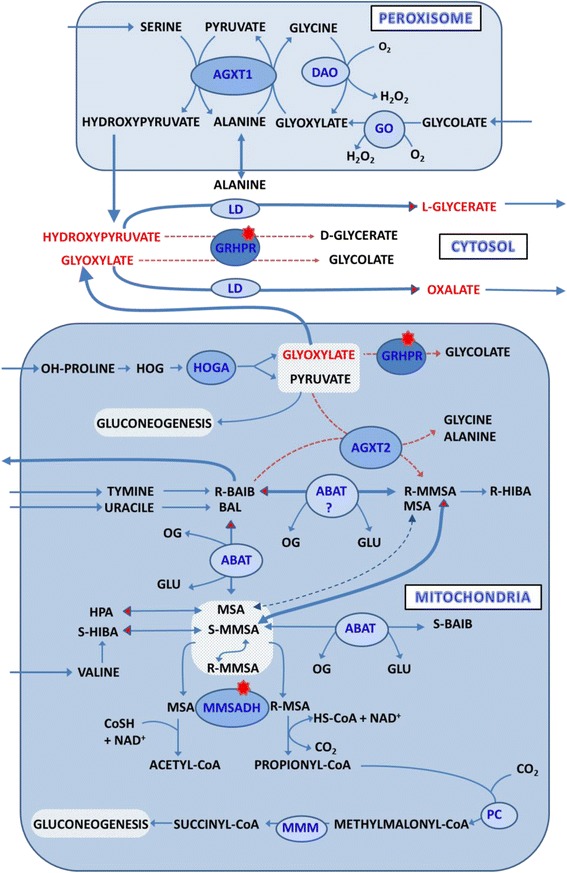

During the attack coupled with febrilities and ketosis, additional metabolic disturbances were observed in the patient which led us to seek other genetic determinants and the elucidation of these findings. Since low amounts of glycolic acid were present in the urine of the patient, we suggest that the AGXT1 enzyme correctly catalyses the conversion of glyoxylate to glycine, and that the detoxification of this harmful metabolite in peroxisomes is effective. The production of glyoxylate in mitochondria by the HOGA enzyme and its detoxification in this compartment is less satisfactorily explained. Based on known data, it can be inferred that except for the GRHPR enzyme, mitochondrial AGXT2 can effectively use pyruvate and glyoxylate also for the transamination of D-3-aminoisobutyrate (D-BAIB) and β-alanine (BAL) [26]. It has been long established that genetic factors influence the high excretion of BAIB, originated preferentially from the degradation of thymine (R- form) and to a lesser extent from valine (S-form) [27–30]. In the patient’s urine we observed an elevated excretion of BAIB, which is usually related to the diminished activities of AGXT2 enzyme. This frequent finding in Caucasians is typically caused by the presence of the five nucleotides variants. In our patient two such variants were found in homozygous state, rs37370 and rs180749, and were referred to in literature as responsible for the loss of AGXT2 activity and increased urinary (BAIB) excretion [18, 19]. According to Landaans and Solen [31], the excretion amounts of this amino acid in urine (95% in the form of R isomer) increased markedly in patients with ketoacidosis, a phenomenon that was also observed in our patient. An important finding was reported by Gennip et al. [32] that urine has a constant ratio between R and S isomers (20:1), supporting the idea that interconversion between enantiomers can occur. It is unequivocally accepted that D-BAIB is generated by the conversion of valine metabolite S-methylmalonyl semialdehyde (S-MMSA) to R- methylmalonyl semialdehyde (R-MMSA), and in the second step to R-BAIB by transamination. A critical point in this claim is transamination because of the stereospecificity of the supposed enzyme ABAT (E.C.2.6.1.19). This enzyme catalyses the transamination of non-stereospecific BAL, GABA and from stereospecific isomers only L-BAIB with 2-oxoglutarate [33, 34]. In a report subsequently published by Tamaki [26], a mixture of appropriate substrates and enzymes AGXT2 and ABAT provide in vitro condition conversion between S-BAIB and R-BAIB. In context with genetic abnormality (AGXT2 deficiency), we consider changes of the mitochondrial pool of HOGA, glyoxylate, and their additive inhibitory effects on GRHPR that accentuate deficiency. Except for the basic biochemical finding related to HP2, the GC/MS analysis of urinary organic acids disclosed an increase in HBA and adipic acid excretion. These observations are in accordance with the health status of our patient with food restrictions that resulted in the increase of ketone bodies and dicarboxylic acids production. In addition, other minor metabolites (HIBA, HPA, EHPA, 2-methyl-3-hydroxybutyrate) were found in elevated quantities in the urine of patients with ketoacidosis [35, 36]. When we compared the excretion of these metabolites in our patient’s urine with control urine samples (to means of values), the excretion of HIBA was elevated 8 times, EHPA 10 times, and HPA even 150 times. Subsequently when we compared the patient’s values with those of patients with ketosis, the elevation for HIBA is 4 times EHPA 3 times, and HPA 20 times. Data regarding the correlation between HBA and other mentioned metabolites in urine from patients with ketoacidosis has been very rare [35]. In our cohort of patients with ketosis, we observed a relationship between HBA and HIBA excretion, but not between HBA and HPA or EHPA. The discrepancy in the degree of excretion of ketone bodies and studied metabolites is apparent at least for HPA in our patient. A possible explanation is that there is an influence of overproduced metabolites such as HOGA and glyoxylate on routes producing these trace metabolites, probably by inhibitory mechanism. Catabolic conditions and amino acid break down probably augment this effect. Inspiring for the assessment of this thesis was data published by Pollitt et al. [37], who reported a child with methylmalonyl semialdehyde dehydrogenase deficiency (MMSADH - E.C. 1.2.1.27). Biochemical findings were characterised by an excessive excretion of amino acids R-BAIB, S-BAIB, BAL, and hydroxyacids such as HPA, S-HIBA and EHPA, and were logical consequences of MMSADH deficiency. Metabolic disorders in the child were confirmed by the finding of a homozygous mutation 1336G > A (Gly446Arg) by Chambliss et al. [38]. Catalytical properties of a rat liver mitochondrial enzyme isolated by Goodwin et al. [39] enable NAD+ dependent dehydrogenation of malonate semialdehyde (MSA) and MMSA. This enzyme participates in the metabolism of valine, thymine, uracile, and their catabolic products such as BAL and both isomers of BAIB. In relation to the metabolism of MMSA kinetic data characterised by Godwin et al. [39], Kedishvili et al. [40] and interconversion studies published by Manning and Pollitt [41] indicate that both stereo isomers are used by MMSADH, though the R isomer is preferred. In our patient all the above-mentioned metabolites (BAL was not measured) show a significant increase in excretion, and are in thin connection with the function of MMSADH. A possible explanation is the inhibitory effect of overproduced metabolites such as HOGA or unconsumed products such as glyoxylate on MMSADH due to the deficiency of GRHPR and AGXT2. In regard to the close structural resemblance to MSA, we consider that glyoxylate may be favorised as the inhibitor of the enzyme. The net of metabolic changes in mitochondria, peroxisomes and cytosol of patient is depicted in Fig. 4.

Fig. 4.

The scheme showed the probably metabolic pathways in patient with PH2 and AGXT2 deficiency. The red dots indicate deficient enzymes, red dashed arrows point to the deficiency of metabolic pathway, thick blue arrows represent the overproduction of enzymes and red ends of the blue arrows point to the overproduced metabolite. Abbreviations: DAO – D-aminoacid oxidase; AGXT1 – alanine-glyoxylate aminotransferase1; GO – glycolate oxidase; LD – lactate dehydrogenase; HOGA - 4-hydroxy-2-oxoglutarate aldolase; AGXT2 – alanine-glyoxylate aminotransferase 2; ABAT – aminobutyrate-2-oxoglutarate; MMSADH – methylmalonyl semialdehyde dehydrogenase; MMM – methylmalonyl-CoA mutase; GRHPR - glyoxylate reductase-hydroxypyruvate reductase; PC – propionylcarboxylase